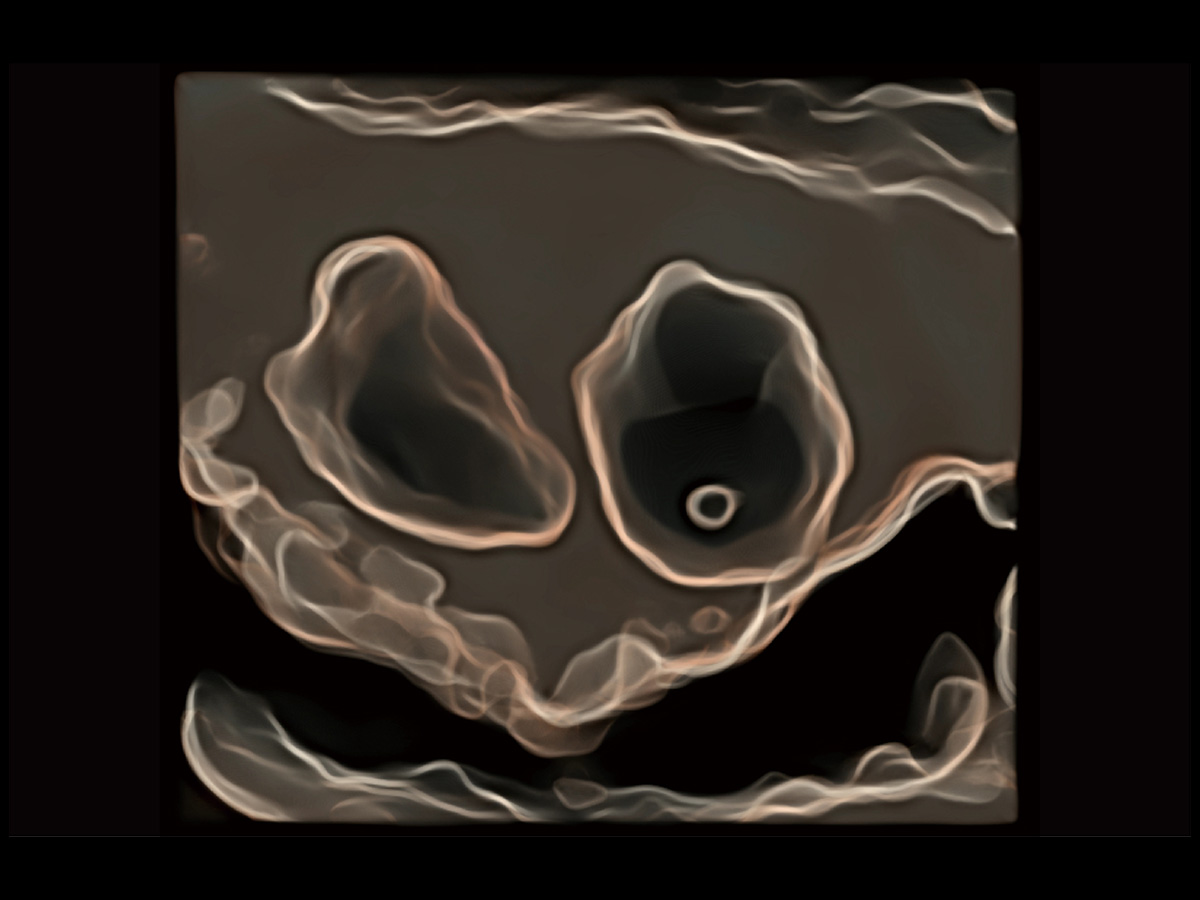

“生育问题”即关系民族复兴,也关系亿万家庭的幸福。随着婚育年龄推迟、社会压力增加等因素,越来越多人群也面临着“生不出、生不好”的问题。辅助生殖作为治疗不孕不育最有效的方法之一,也逐渐成为育儿新希望。而超声检查能为生殖需求人群的初诊评估提供宝贵的信息。 P20 Elite是开立医疗匠心打造的一款生殖应用型彩超。她继承开立医疗高端极光平台,突破性地将多款新型芯片及硬件模块进行整合,均衡了高端系统性能与小巧灵动机身。P20 Elite卓越的图像质量搭载专科探头,旨在为您提供全面的辅助生殖解决方案。

P20 Elite配备了丰富的生殖探头群和临床应用功能,在卵泡监测、穿刺取卵、胚胎移植、妊娠确认等领域,为生殖需求人群提供了新的临床机会,重新定义高端超声如何应用于生殖健康检查。